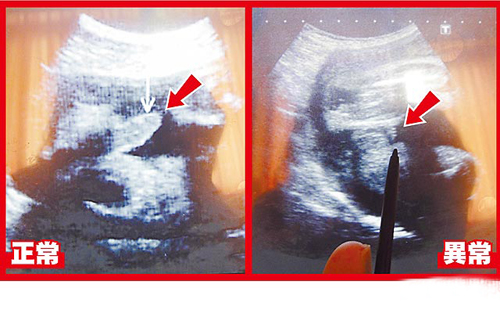

超聲波可看到胎兒生殖器,左圖箭頭處為28周正常男嬰生殖器:右圖箭頭處為異常男嬰28周時生殖器畫面。圖片來源:臺灣媒體

據報道,臺中大里仁愛醫院婦產科醫師李瑞祺說,這名30歲產婦在懷孕28周時出現密集陣痛,醫院緊急幫她安胎、進行超聲波等檢查,赫然發現胎兒生殖器特別短,陰囊還是空的,懷疑染色體或基因異常導致生殖器過短與隱睪癥。但孕婦在26周時曾進行羊膜穿刺檢查,顯示性染色體正常。